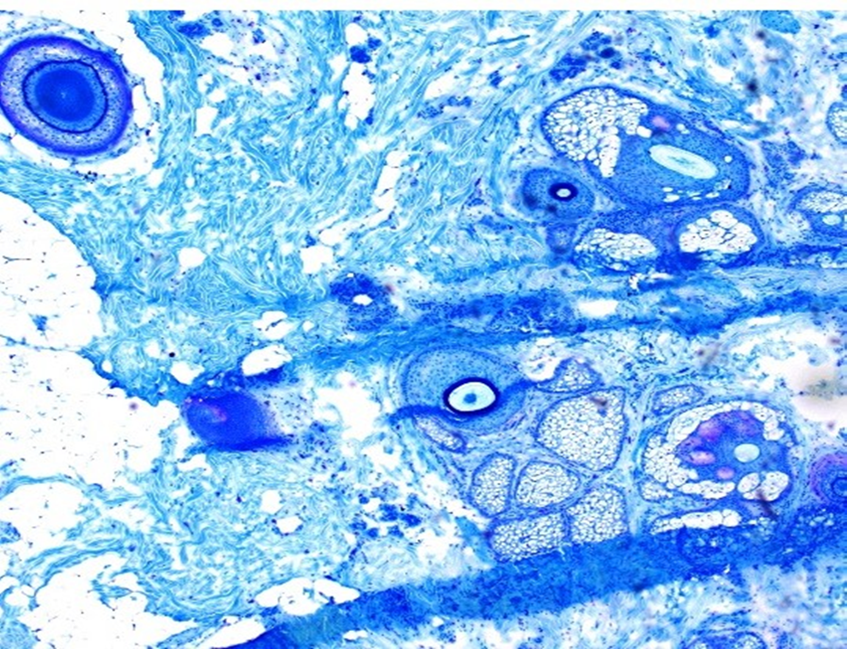

Reticulin Staining - BMT Scheme

This is an excellent example of retuculin staining. The silver has impregnated course and fine fibre networks with high specificity.

This scored 9/10.